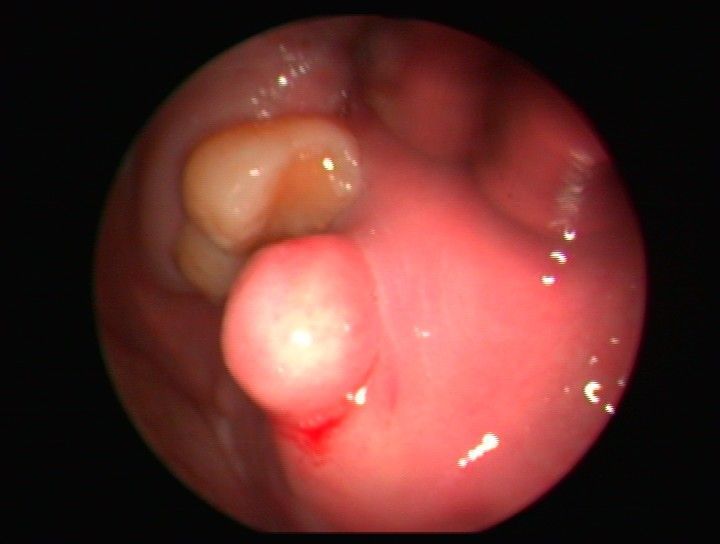

Nuestro servicio de otorrinolaringología en Vigo ofrece atención especializada para el diagnóstico y tratamiento de problemas de oído, nariz y garganta. Trabajamos con un enfoque cercano y profesional para resolver desde molestias comunes hasta patologías más complejas. Valoración de daño auditivo y peritajes.

En nuestra clínica, nos enfocamos en proporcionar soluciones efectivas para una variedad de problemas relacionados con la salud del oído, nariz y senos paranasales. Nuestro objetivo es ofrecer tratamientos avanzados y personalizados a cada paciente.